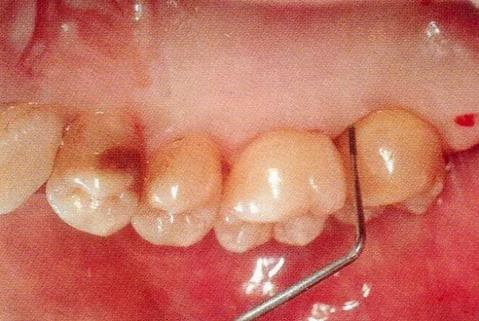

▼圖14-1 術(shù)前的狀態(tài)。近中存在10mm的牙周袋。